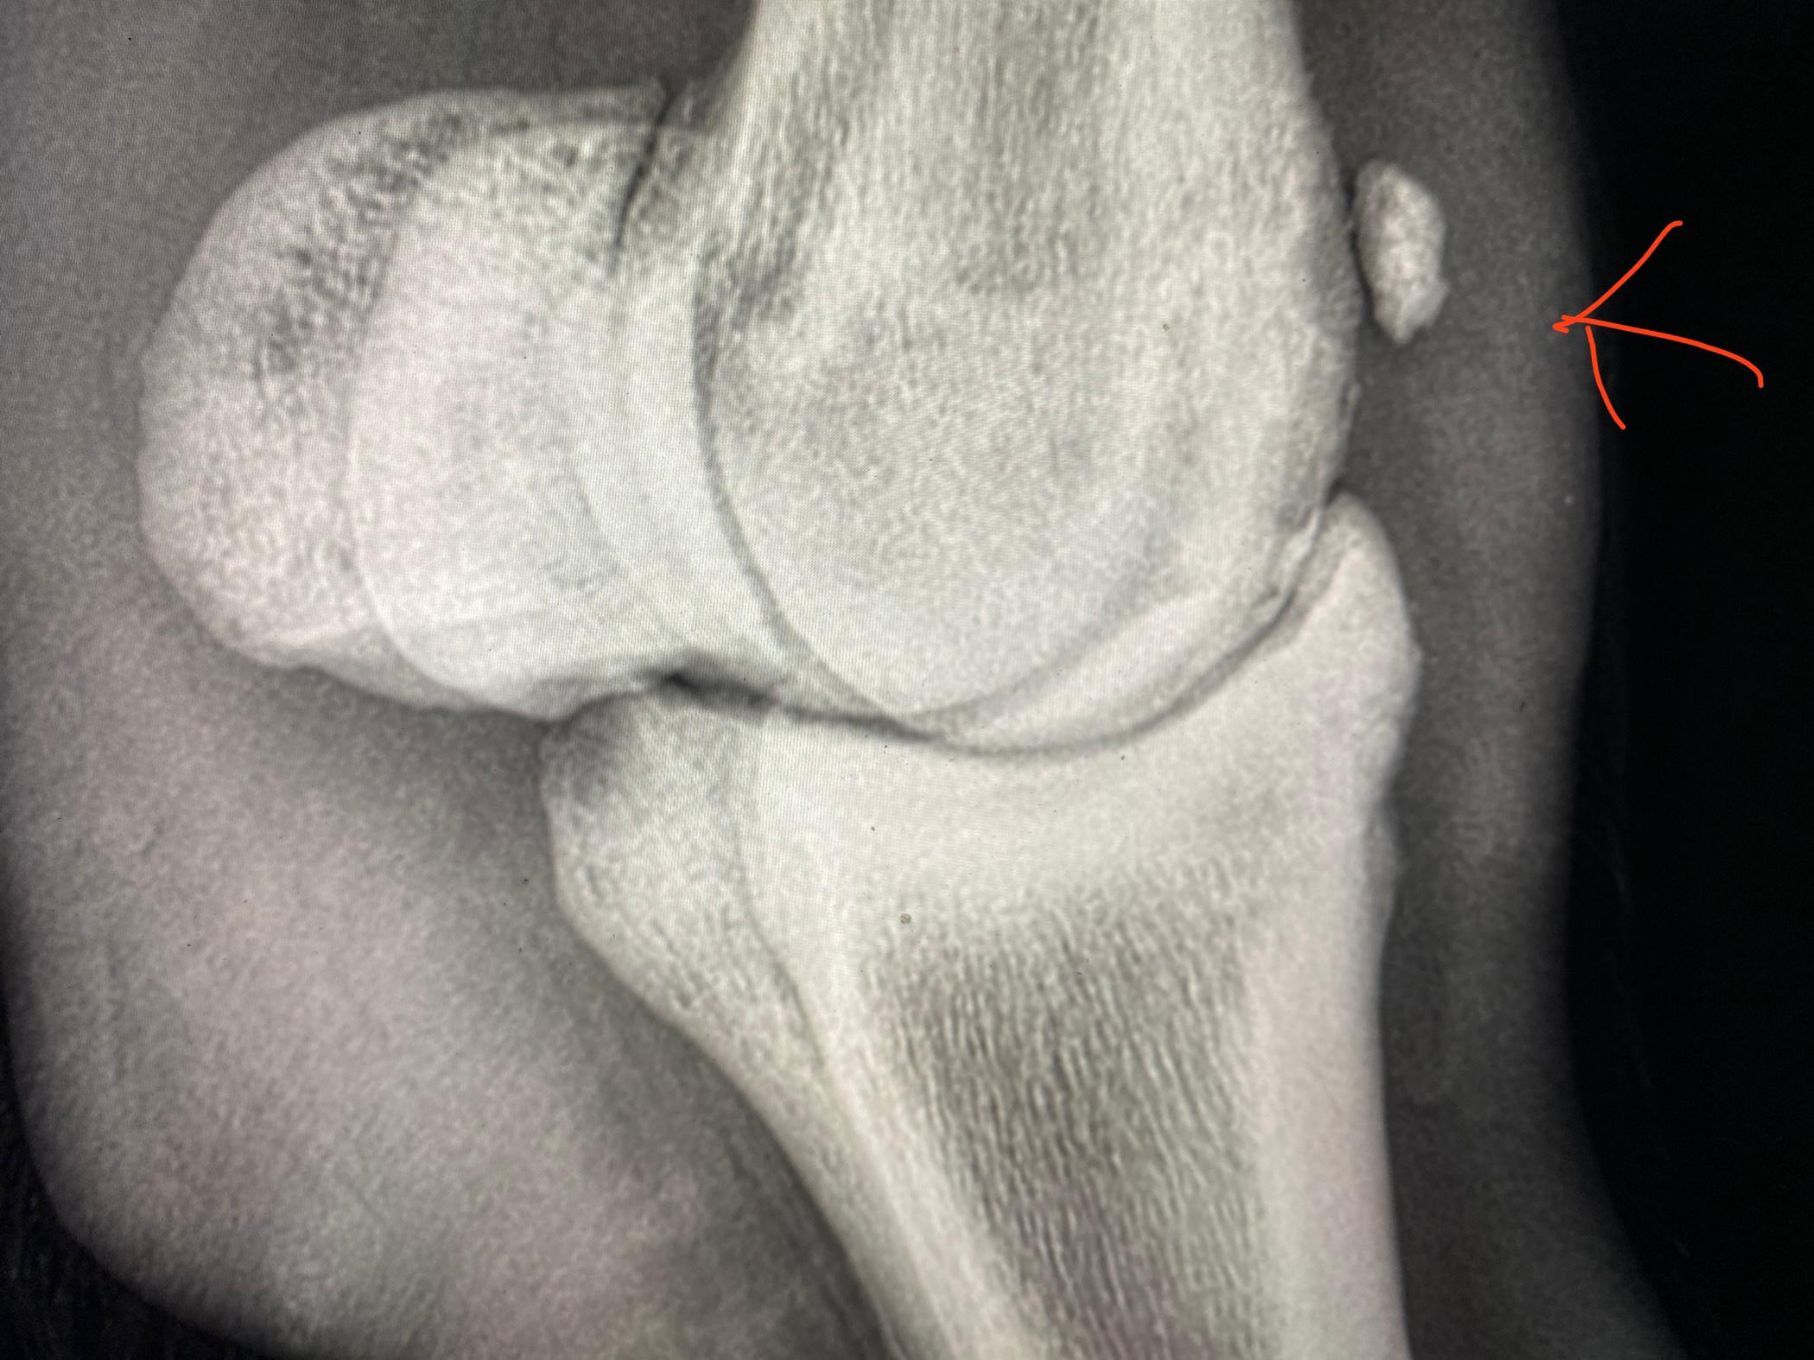

Atendemos los caballos enfermos, para lo cual se cuenta con una unidad móvil, equipada con aparato de rayos X, ecógrafo y de bioquímica sanguínea. Así mismo, realizamos las cirugías viables en el campo.